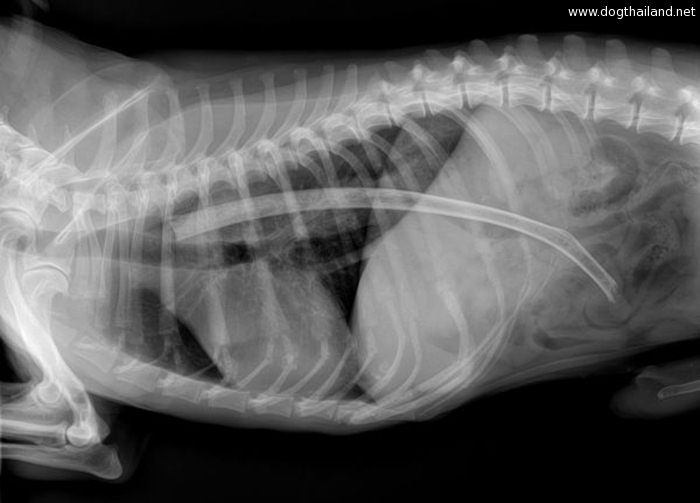

โดยทางเว็บไซต์ทเวนตี้มินูทเท็น ของสวิตเซอร์แลนด์ ได้เผยแพร่ภาพเอ็กซเรย์ภายในท้องของสัตว์เลี้ยงหลากหลายชนิดด้วยกัน ซึ่งแต่ละภาพนั้นชวนให้สยดสยองเป็นอย่างมากเลยทีเดียว

เพราะเมื่อแพทย์เห็นฟิล์มเอ็กซเรย์ก็ถึงกับผงะ และช็อคไปเลยทีเดียว จนต้องรับทำการล้างกระเพาะอาหารให้กับสัตว์เลี้ยงเหล่านี้อย่างเร่งด่วนทันที เเนื่องจากในกระเพาะของสัตว์เลี้ยงเหล่านี้เต็มไปด้วยสิ่งแปลกปลอมมากมาย ที่ไม่น่าเชื่อว่า "จะกินได้...?" นั่นเอง จะมีอะไรบ้าง ไปดูกันเลย

7. ภาพเอกซเรย์ภายในท้องของสุนัขตัวหนึ่ง ที่เต็มไปด้วย "เชือก"